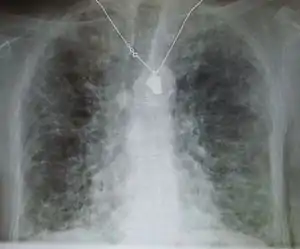

A chest X-ray demonstrating pulmonary fibrosis due to amiodarone.

Side effects of amiodarone include various pulmonary effects.[22] The most serious reaction that is due to amiodarone is interstitial lung disease. Risk factors include high cumulative dose, more than 400 milligrams per day, duration over two months, increased age, and preexisting pulmonary disease. Some individuals were noted to develop pulmonary fibrosis after a week of treatment, while others did not develop it after years of continuous use. Common practice is to avoid the agent if possible in individuals with decreased lung function.

The most specific test of pulmonary toxicity due to amiodarone is a dramatically decreased DLCO noted on pulmonary function testing.